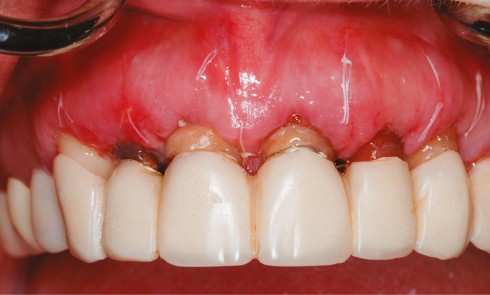

Article réservé à nos abonnés Harmonisation des collets avec allongement de couronnes cliniques

L’esthétique du sourire impose la recherche d’un équilibre entre le parodonte et les dents, d’une harmonie entre le rose et...